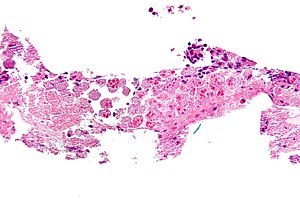

Amebiasis. H&E stain. | |

| LM | entamoeba histolytica: round/ovoid eosinophilic bodies ~ 40-60 micrometers in maximal dimension; found in bowel lumen, usu. ingest (whole) red blood cells |

- Entamoeba histolytica are round/ovoid eosinophilic bodies ~ 40-60 micrometers in maximal dimension.

- Found in bowel lumen.

- Ingest RBCs.